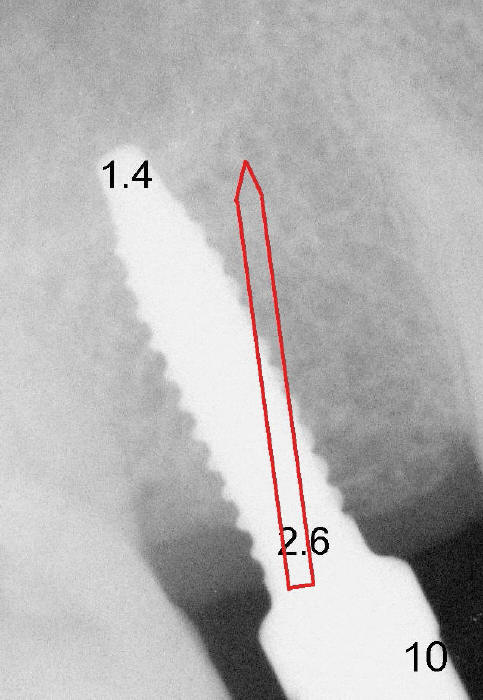

Another drawback of the implant placement is that the trajectory is off and distal (Fig.3-6), probably due to the low bone density in the distal aspect of the socket prior to extraction (Fig.7 CT sagittal section; MB: mesiobuccal root). The pilot drill must inadvertently have drifted distally and to the less dense bone (Fig.8). If it had been found, it could have been corrected early (Fig.9 red arrow). The trajectory could have been corrected immediately after the 2.6 mm expander (Fig.10). Ideally the pilot drill (Fig.11arrow) should be placed slightly mesial to the presumably mid edentulous line (red line) and only half of the length. If the trajectory is right, continue osteotomy (Fig.12). If not, correct it immediately.